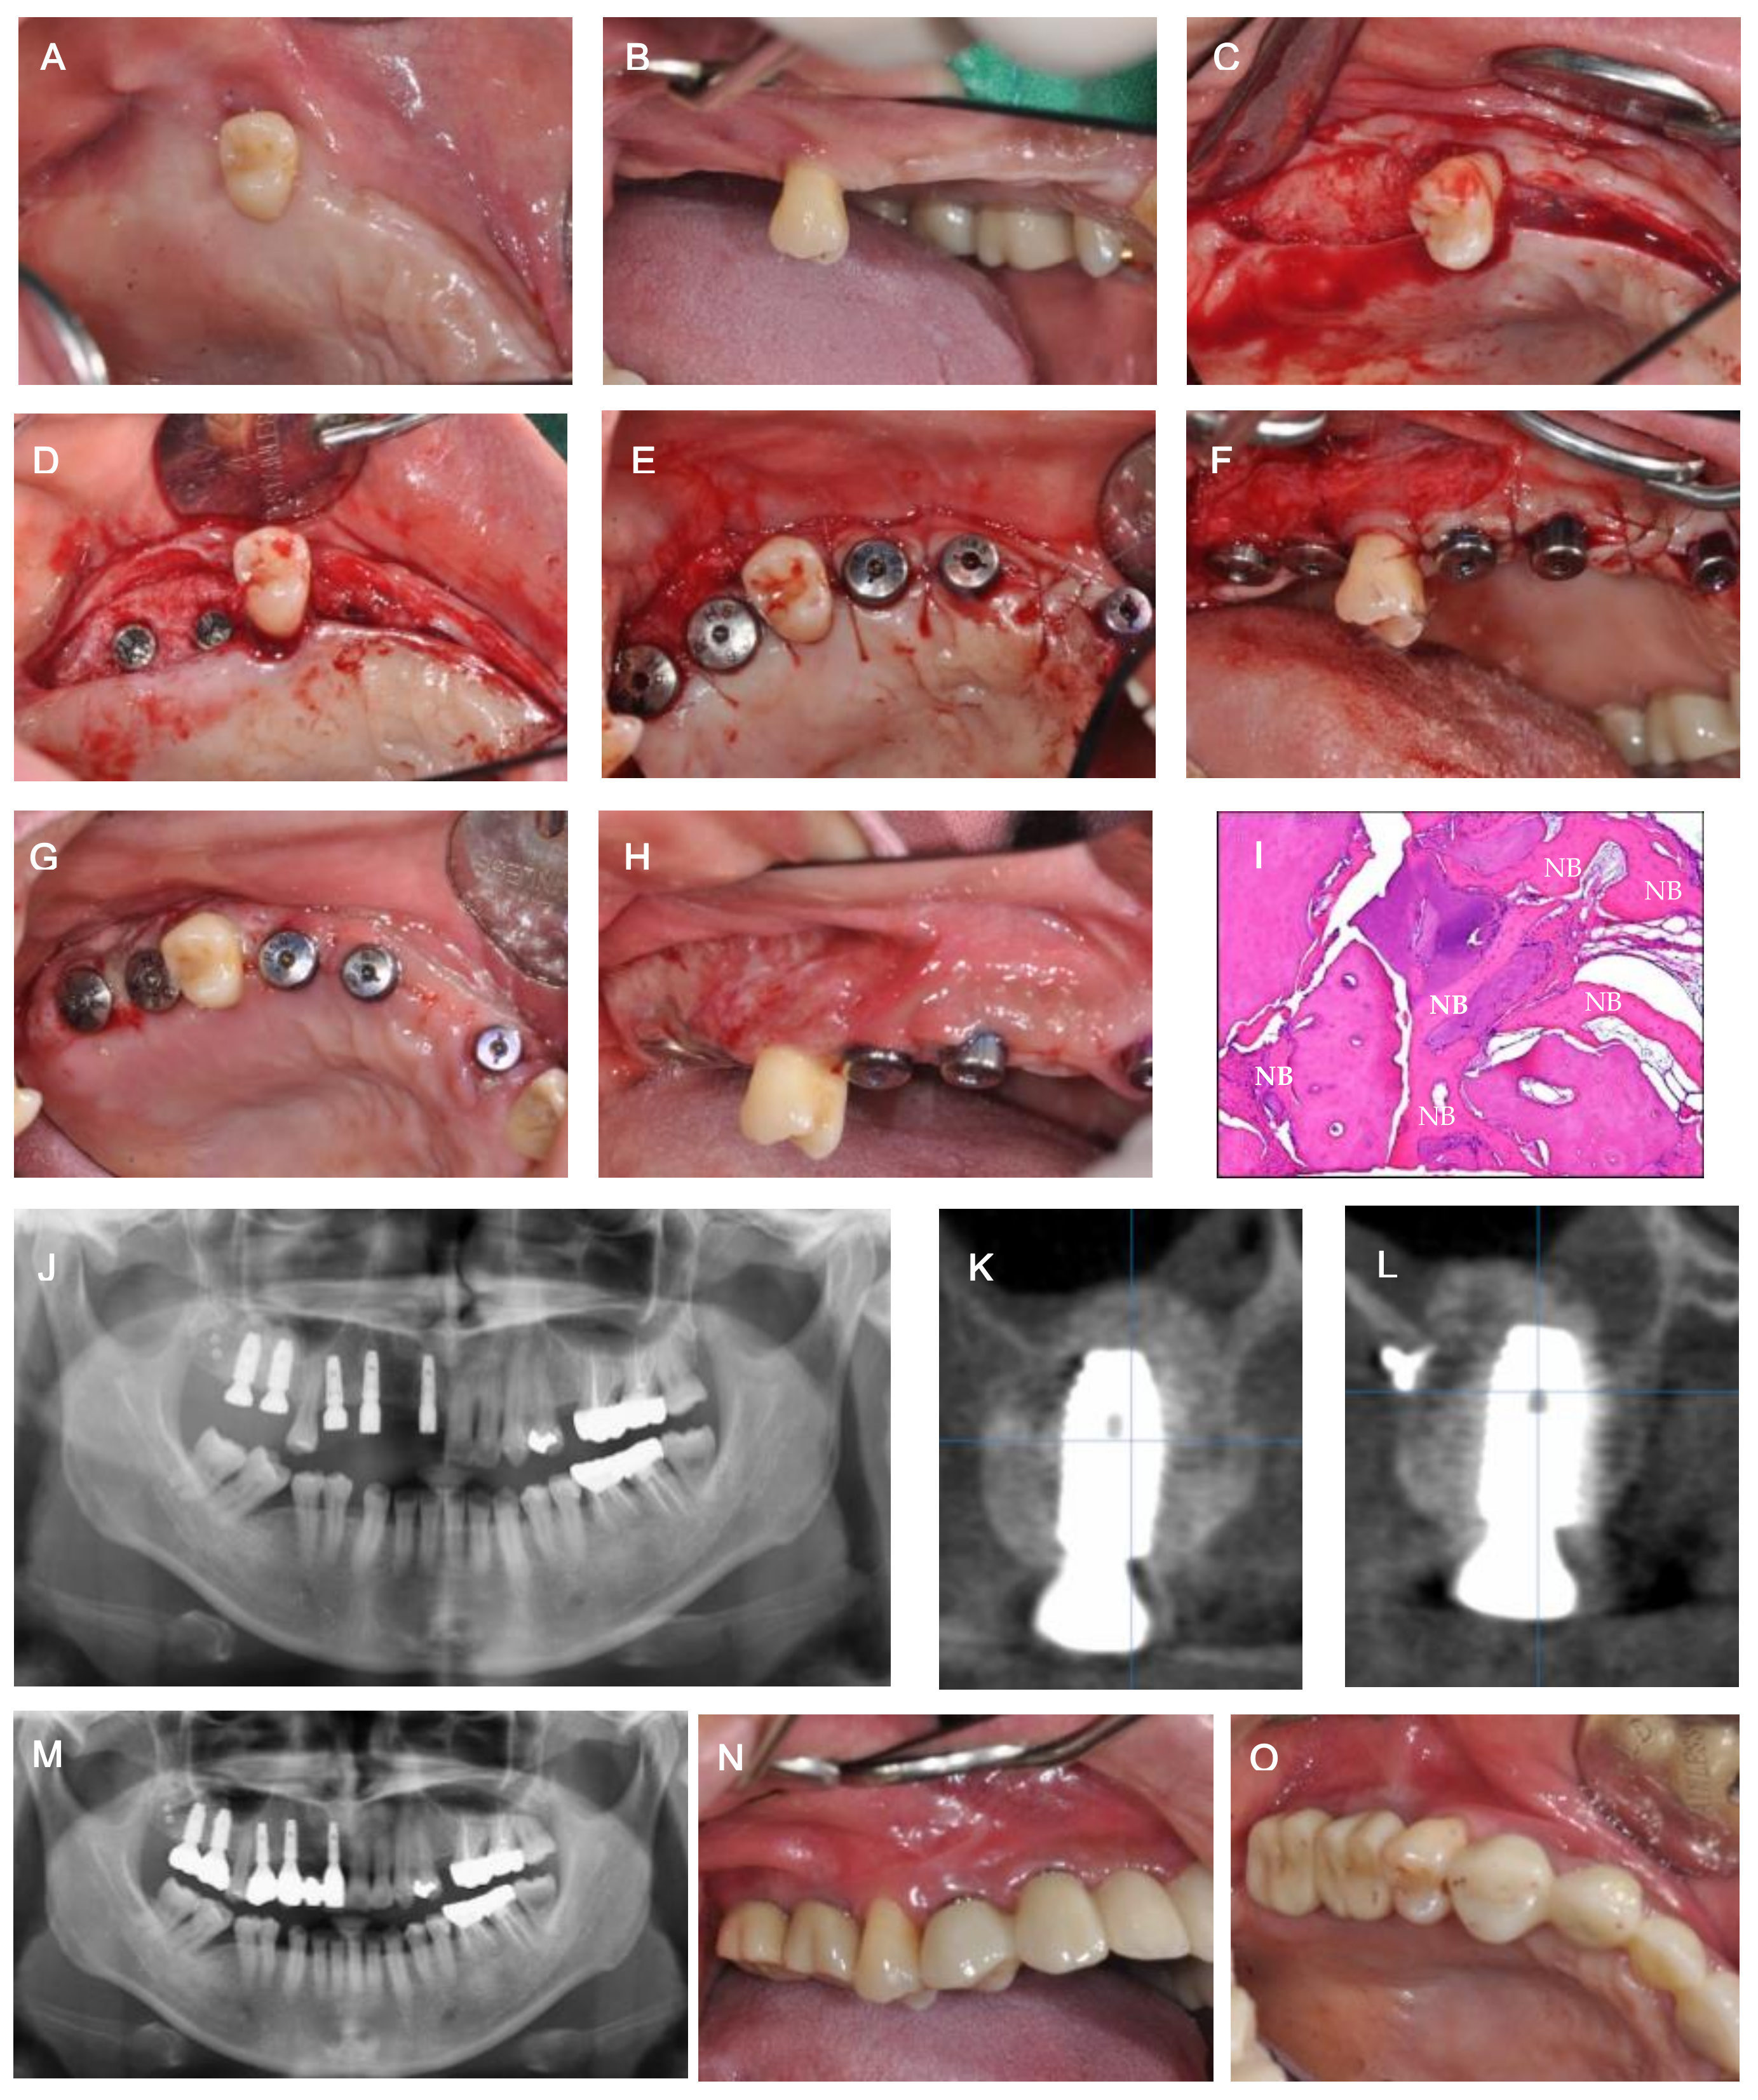

2. Case Description